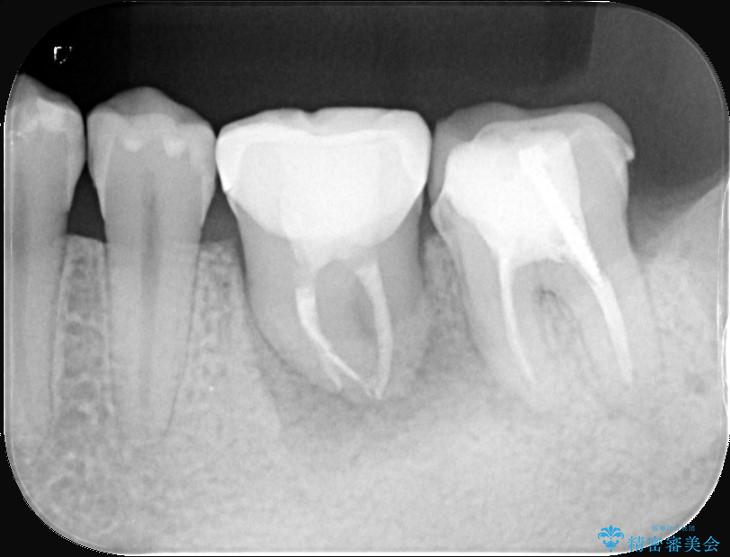

- 主訴:左下6番目の歯の周りが痛くなり、他院で診てもらったが抜歯と言われてしまった。ネットで歯牙移植というものを知りやっている医院を探している。

左下6番目の歯の周りに大きく透過像を認め、再根管治療後の予後が良くない可能性が大きく当院でも抜歯適用歯と説明しました。欠損部に対しインプラント治療や歯牙移植(左下の親知らずの移植)、ブリッジを提案し、歯牙移植を行うこととなりました。

保存が難しい左下6番目の歯を抜歯し、左下8番目の歯(親知らず)を抜歯窩に移植しました。歯牙移植後の動揺防止のため暫間固定を行っています。

また移植後2週間経過時点で根管処置が必要となります。